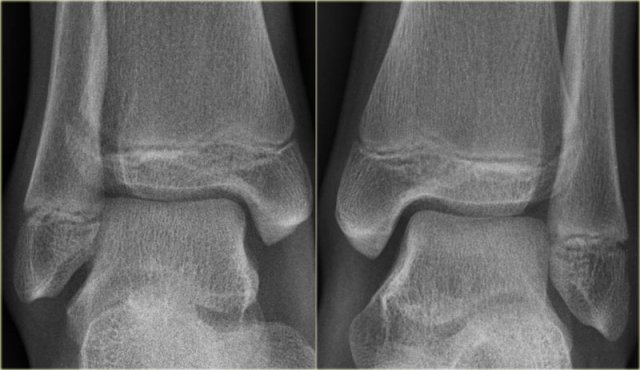

Study the images and then scroll to the next images.

The fracture through the epiphysis can be easily missed (blue arrow).

The fracture through the growth plate is only seen on CT.

Continue with the CT images.

The CT-images nicely display the fracture through the growth plate and the epiphysis.